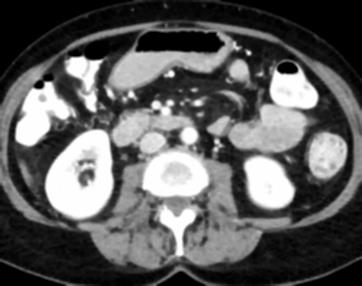

Due to the constraints of the imaging device and high cost in operation time, computer tomography (CT) scans are usually acquired with low intra-slice resolution. Improving the intra-slice resolution is beneficial to the disease diagnosis for both human experts and computer-aided systems. To this end, this paper builds a novel medical slice synthesis to increase the between-slice resolution. Considering that the ground-truth intermediate medical slices are always absent in clinical practice, we introduce the incremental cross-view mutual distillation strategy to accomplish this task in the self-supervised learning manner. Specifically, we model this problem from three different views: slice-wise interpolation from axial view and pixel-wise interpolation from coronal and sagittal views. Under this circumstance, the models learned from different views can distill valuable knowledge to guide the learning processes of each other. We can repeat this process to make the models synthesize intermediate slice data with increasing inter-slice resolution. To demonstrate the effectiveness of the proposed approach, we conduct comprehensive experiments on a large-scale CT dataset. Quantitative and qualitative comparison results show that our method outperforms state-of-the-art algorithms by clear margins.

翻译:由于成像装置的限制和操作时间成本高,计算机断层扫描通常以低切片分辨率获得。改进切片内分解法有利于人类专家和计算机辅助系统进行疾病诊断。为此,本文件制作了新的医疗切片合成法,以增加解片之间的解析。考虑到临床实践中总是没有地面真相中间医疗切片,我们采用渐进的跨视图相互蒸馏战略,以自我监督的学习方式完成这项任务。具体地说,我们用三种不同的观点来模拟这一问题:从轴视中切片间解法和从正弦和方位角度对等离子间解法。在此情况下,从不同观点中学习的模型可以提取宝贵的知识,用以指导彼此的学习过程。我们可以重复这一过程,使模型合成中间切片数据,同时增加分裂分辨率。为了证明拟议方法的有效性,我们在大规模CT数据集上进行了全面的实验。通过清晰的定量和定性的算法比较结果显示,我们的方法将超越了一种方法。